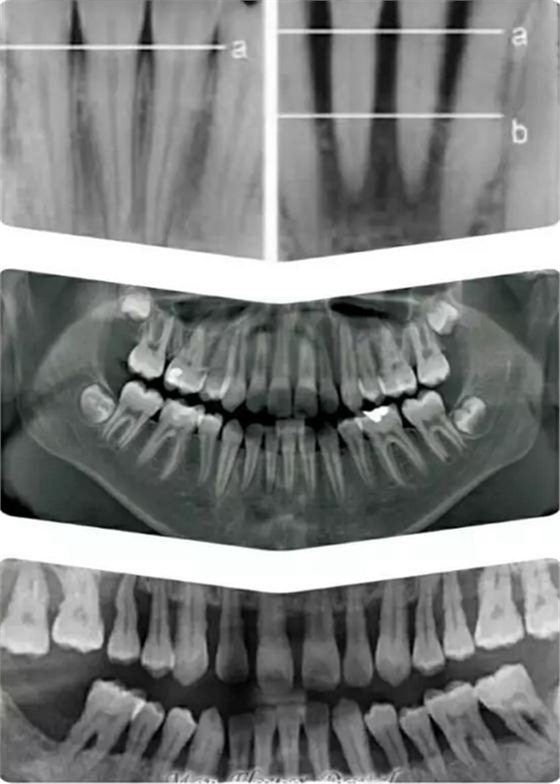

如上圖所示。 牙周這個詞或許有點陌生,它指的是牙齒周圍,包埋著牙根的硬質(zhì)的牙槽骨,和覆蓋其上肉眼可見的粉色牙齦。

牙槽骨對牙齒起主要固定支撐作用,并且一般只能在X 光片上顯示;牙齦是保護牙槽骨的第一道屏障。

在上圖X光顯示下,牙槽骨從正常水平 a 線萎縮到了b 線(中圖為正常全口X光牙片,最下圖為全口重度牙周病X光片),以至不能再固定支撐牙齒,就象埋在電線桿周圍的土被挖掉,電線桿只能逐漸倒伏一樣。